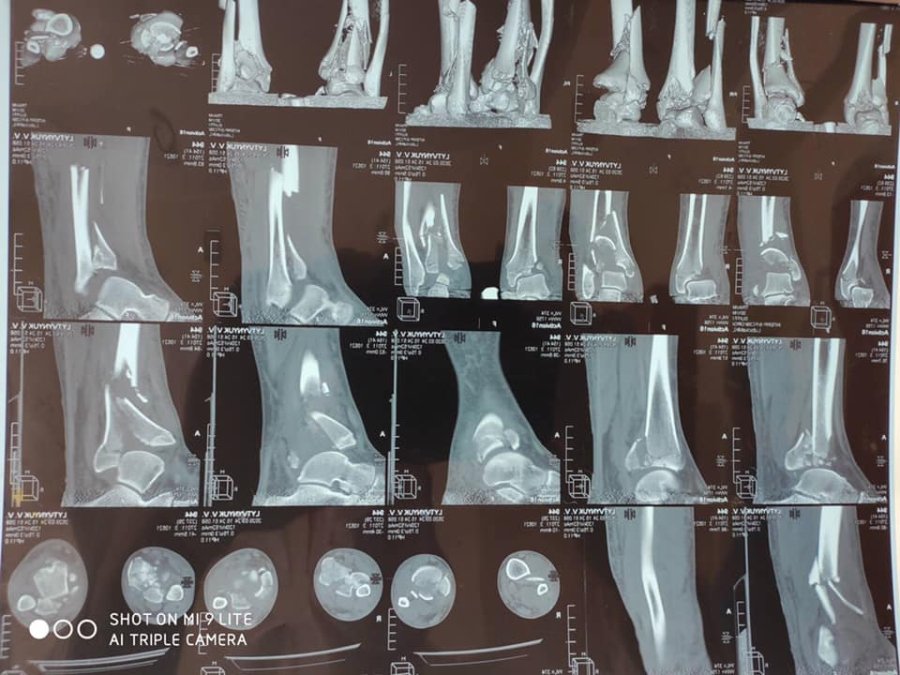

"У відділенні лікувався хворий, який впав з 4-х метрової висоти з переломом обох нижніх кінцівок. Йому успішно зробили оперативне втручання - металоостеосинтез дистальних метаепіфізів правої і лівої нижніх кінцівок з кістковою пластикою", - розповів лікар ортопед-травматолог Леонід Шеремета.

Медики міської лікарні застосовують кращі практики сучасних технологій остеосинтезу, зокрема мінімально-інвазивні методи (Minimally Invasive Plate Osteosynthesis MIPO) фіксації переломів з використанням пластин з кутовою стабільністю.

Перевагою цього методу лікування є збереження функціональної рухомості кінцівки та найближчих суглобів в період зрощення, прискорення консолідації та відновлення опорної функції кінцівки.

Загальноприйняті принципи остеосинтезу — стабільність (нерухомість уламків, що створює умови для зрощення кісток) та функціональність (можливість рухати кінцівкою, при цьому зберігається кровопостачання, попереджається розвиток контрактури, атрофії м'язів).